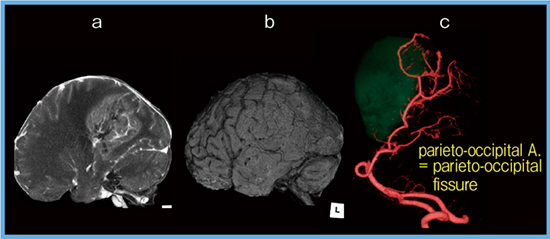

前交通動脈瘤の術前をAquilion Precision(図1 b)で,術後を従来CTのAquilion PRIME(図1 a)で撮影した症例を示す。いずれも造影剤投与法や撮影タイミングは同一である。Aquilion Precisionは従来CTに比べ,主幹動脈皮質枝末梢まで良好な描出が得られている。 Aquilion Precisionは空間分解能が飛躍的に向上したが,一方でノイズ成分も増加する。当院では,2017年9月に導入されたFull IRの逐次近似再構成技術“FIRST”を用い,ノイズ低減と描出能向上を図っている。FBP,AIDR3D,FIRSTを用い皮質枝や穿通枝動脈の描出能を比較した結果,FIRSTで連続した良好な描出が得られた。

図1 前交通動脈瘤症例の描出能の比較

中大脳動脈は内頸動脈から分岐した後,シルビウス裂を通り脳表に出て,大脳皮質に複数の皮質枝を分岐する。近位部よりM1〜M4の4つのsegmentに分けられる。脳表を走行する部分はM4 segmentに相当し,内頸動脈や中大脳動脈の高度狭窄,閉塞症例においてSTA(浅側頭動脈)とMCA(中大脳動脈)とを吻合し血流を改善させるSTA-MCAバイパス術の際に重要であるが,従来CTでは描出が困難であった。Aquilion Precisionではrecipient血管のM4 segment,donor血管の浅側頭動脈の前頭枝・頭頂枝ともに末梢まで良好に描出可能で(図2 a, b),さらに,脳表画像とフュージョンさせることで脳回と各血管との位置関係を把握でき,吻合血管や吻合箇所の術前シミュレーションに有用である(図2 c)。

図2 中大脳動脈皮質枝,前頭枝,頭頂枝